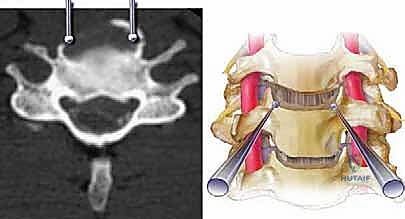

الخطوة 4: زراعة الدعامة والدمج العظمي (Fusion)

بعد إزالة الفقرة، يتبقى فراغ كبير. لإعادة بناء العمود الفقري، يتم إدخال دعامة معدنية أو قفص من مادة (PEEK) أو التيتانيوم، مملوء بطعم عظمي (يؤخذ عادة من بنك العظام أو من حوض المريض، أو يتم استخدام بدائل عظمية صناعية). هذه الدعامة تحافظ على ارتفاع الرقبة الطبيعي.

الخطوة 5: التثبيت بالشريحة والمسامير

لضمان ثبات الدعامة ومنع حركتها حتى يكتمل الالتحام العظمي (الذي يستغرق عدة أشهر)، يتم تثبيت شريحة معدنية من التيتانيوم على الجزء الأمامي من الفقرات السليمة (التي تقع أعلى وأسفل الدعامة) باستخدام مسامير طبية خاصة.